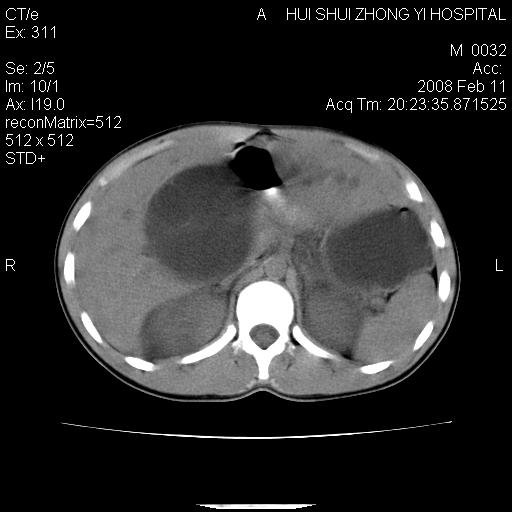

8年前曾在贵洲省人民医院b超诊断为肝内胆管结石。现腹痛剧烈,现发烧、头痛、恶心呕吐县医院b超示胆囊肿大大小159*46mm,囊内见6*5mm强回声光团,胆各总管内径56mm。提示:胆囊结石、急性胆囊炎、胆总管重度扩张。

胆囊结石.急性胆囊炎.重度胆管扩张.右侧胸腔少量积液,建议ct增强

考虑先天性胆管囊肿;胆囊增大并结石。右侧胸腔少量积液,建议ct增强。

caroli囊肿并囊内结石。胆囊增大并胆结石。典型!

先天性胆管囊肿,胆囊结石、胆囊增大,右侧少量胸腔积液。